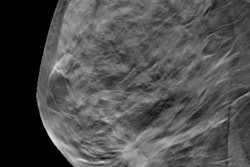

Researchers analyzed websites of 606 U.S. breast cancer centers and found that of those that recommended an age at which to start screening, 87.2% recommended that women begin at age 40, which the authors maintained contradicts guidance from national societies. And of those that provided a screening age as well as a screening interval, 80.9% recommended annual screening starting at the age of 40.

In contrast, the USPSTF guidelines for screening mammography, last updated in 2016, advise screening every two years between the ages of 50 and 74 and that screening for women in their 40s should be based on an individual evaluation of risks and benefits. The American Cancer Society (ACS) recommends annual screening for women between the ages of 45 and 55.

Out of 606 breast centers considered in the study, 487 (80.4%) provided recommendations for screening on their websites. And of these, 429 (88.1%) recommended a starting age and a screening interval.

| Screening recommendations from U.S. breast cancer centers | |

| Starting age | Percent recommending |

| 40 | 77.2% |

| 45 | 7.2% |

| 50 | 4.1% |

| Discuss with physician | 11.5% |

| Screening interval | Percent recommending |

| Annual | 72.7% |

| Annual or biennial | 12.1% |

| Biennial | 3.3% |

| Discuss with physician | 11.9% |